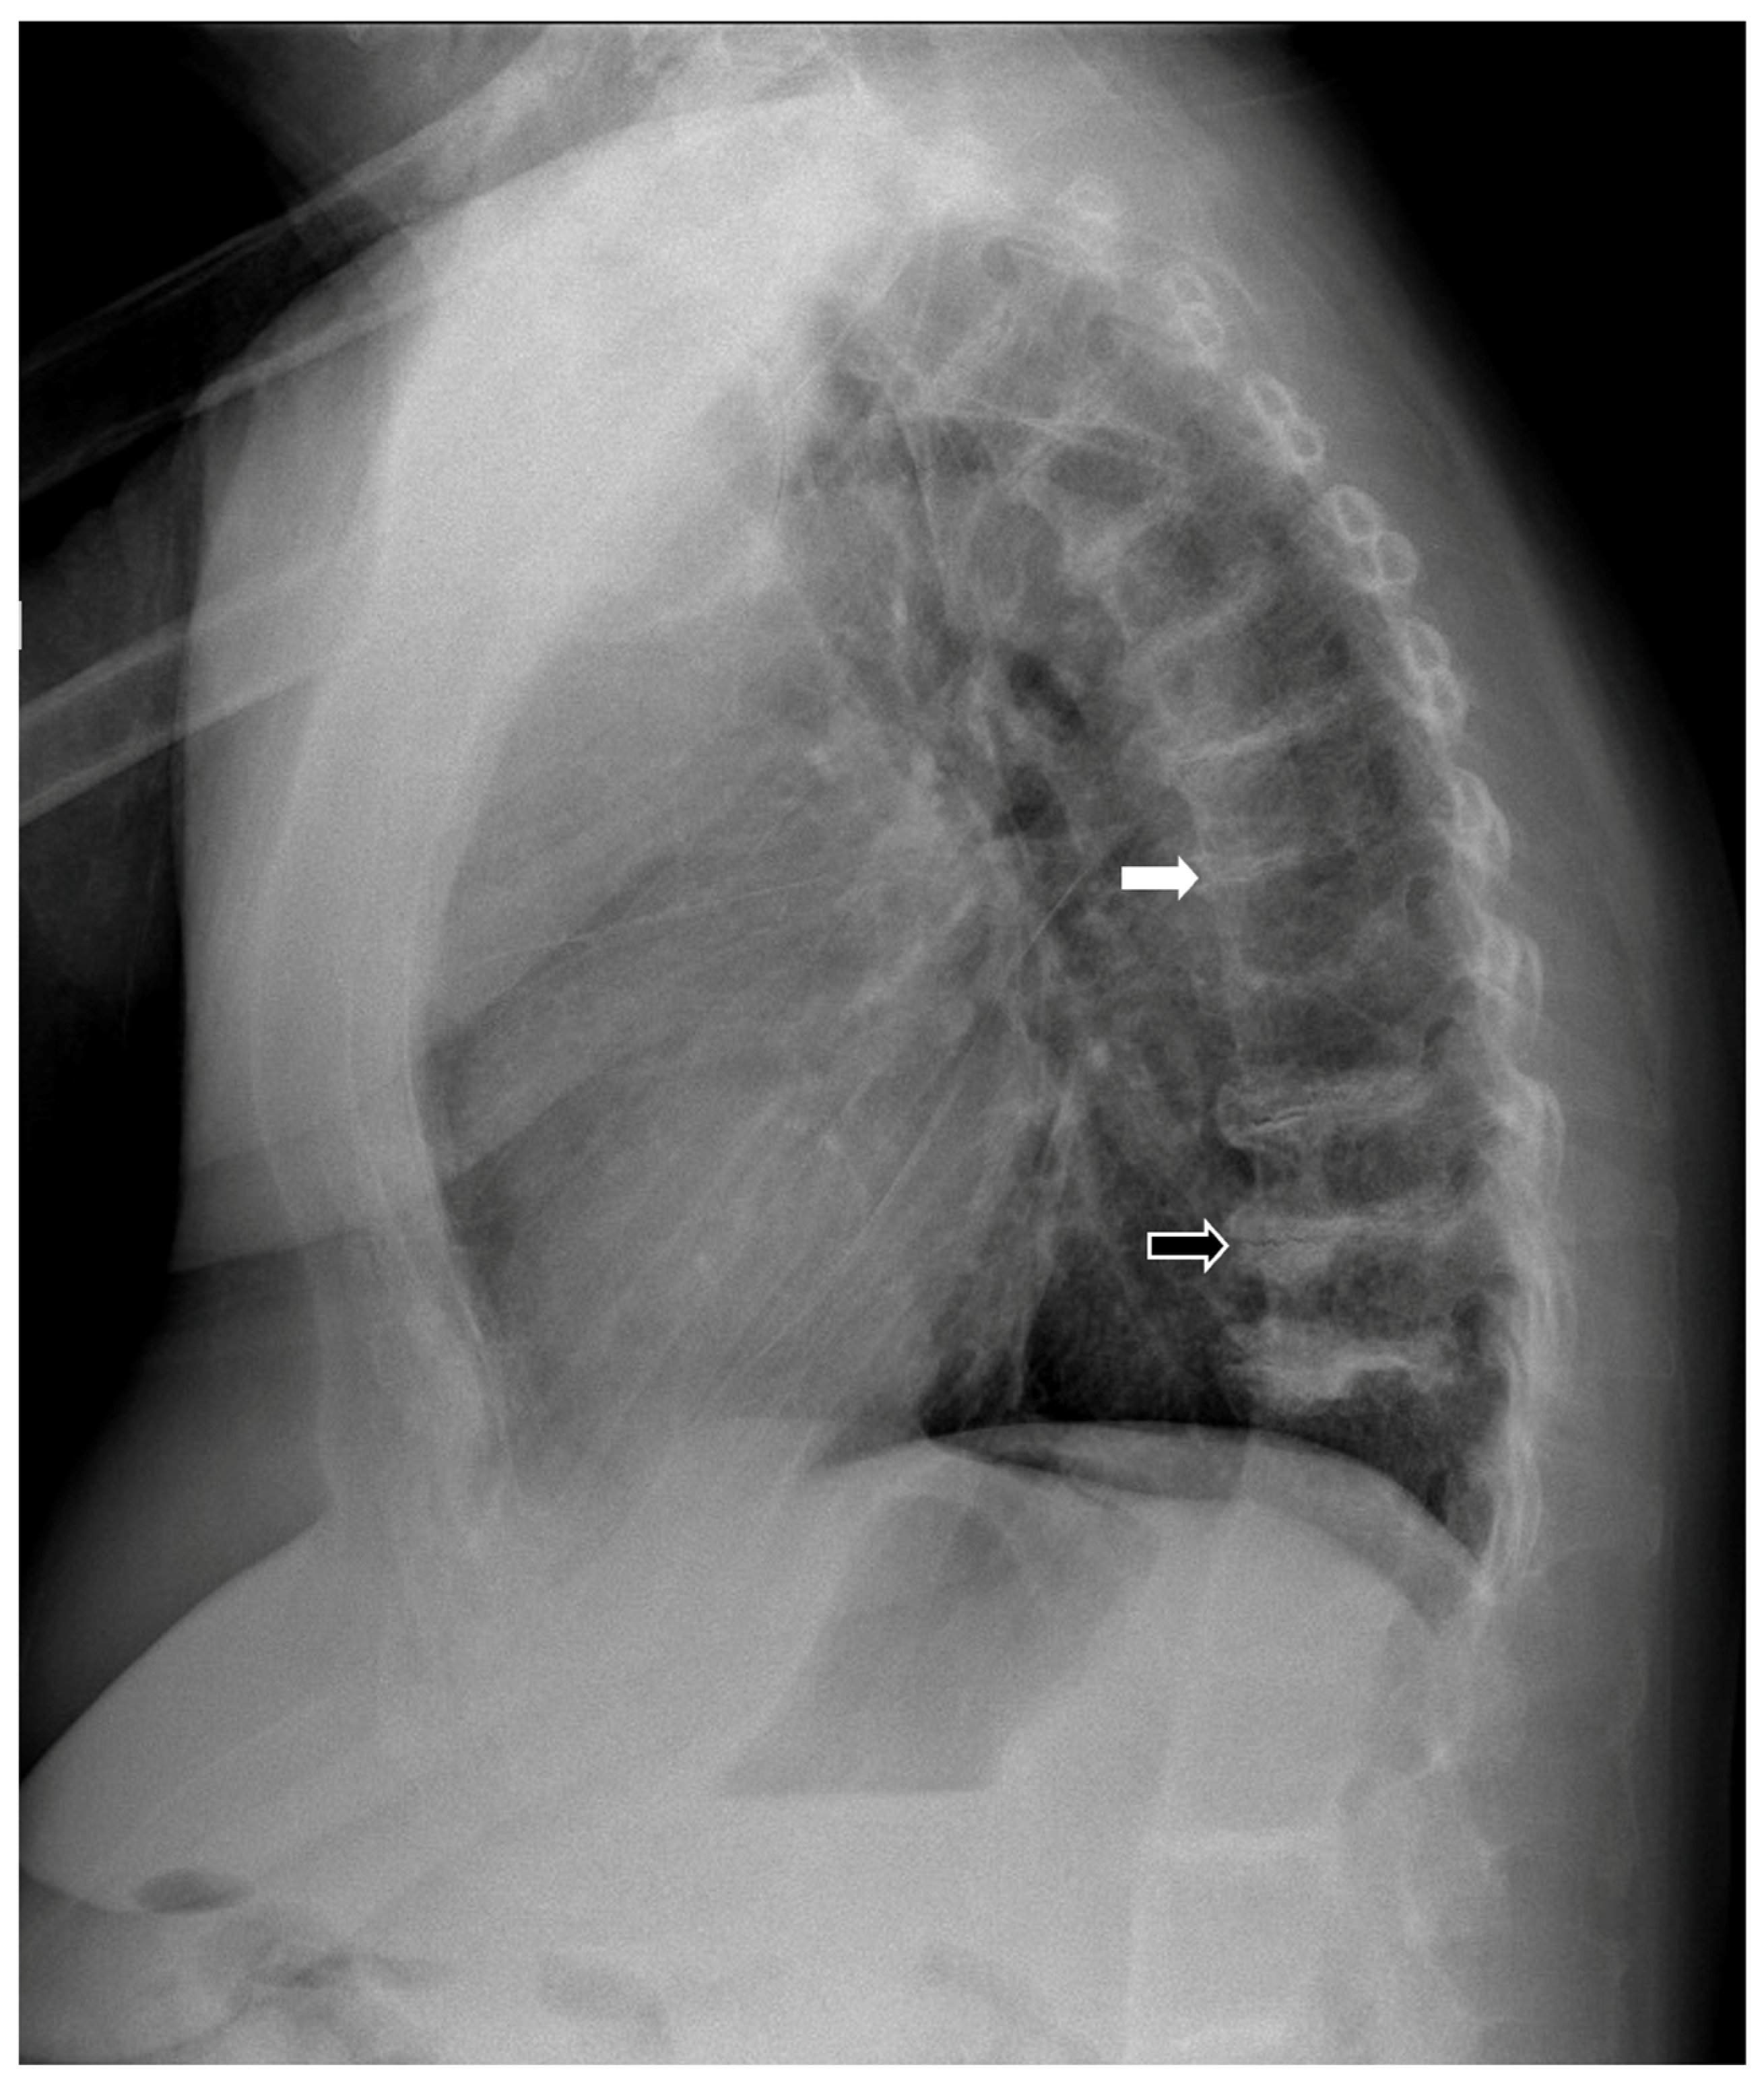

2. Case Report